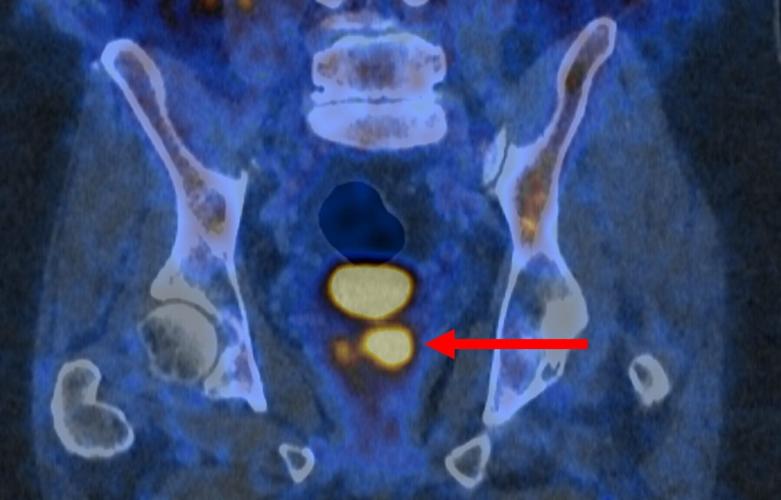

Glowing prostate cancer cells PSMA PET 2. (PRIMARY 2 via SWNS)

Clinically significant prostate cancer (left, PSMA PETCT) despite normal MRI (right, MRI). (PRIMARY2 via SWNS)